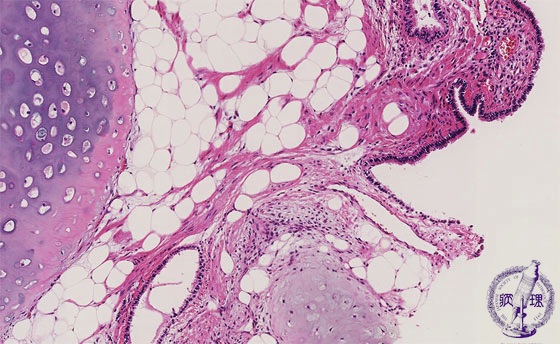

Microscopic view (HE stain, Middle-power-view): The cartilage, adipose tissue and bronchial epithelium show no evidence of cellular or structural abnormality. In addition, smooth muscle, collagenous tissue and or myxomatous elements may be intermingled.